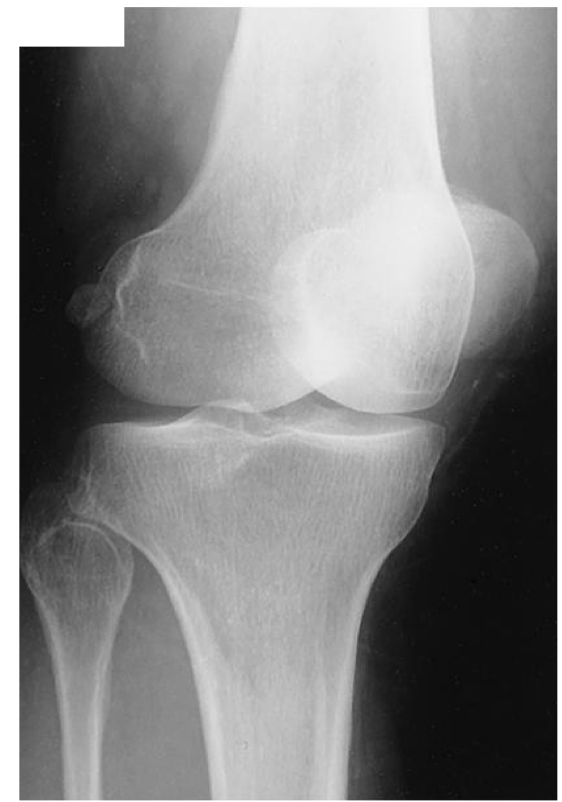

Evaluation Criteria for AP knee

• Femorotibial joint space open

• Femoral condyles are symmetrical

• Femoral epicondyles in profile

• Knee joint centered to collimation field

• Articular facets of tibia on end

• Intercondylar eminence centered within the fossa

• Intercondylar fossa is barely seen

• Approx ½ of fibular head superimposed by tibia

• Head of fibula approx 1.25 cm from tibial plateau

• Patella sits slightly lateral to midline